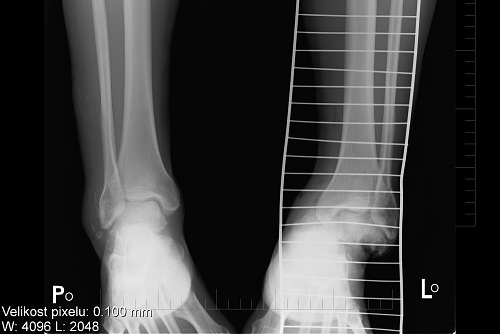

Pak už následují ty obligátní věci jako injekce, rentgeny, operace ... bilance je neslavná. Zlomené hlezno a rozdrcená pata na pravé noze, otevřená zlomenina kotníku s vyhozeným kloubem, zlomené hlezno na levé. To bude asi na dlouho.

Moje nožičky

foto by © Archive Aldo

Měsíc po pádu